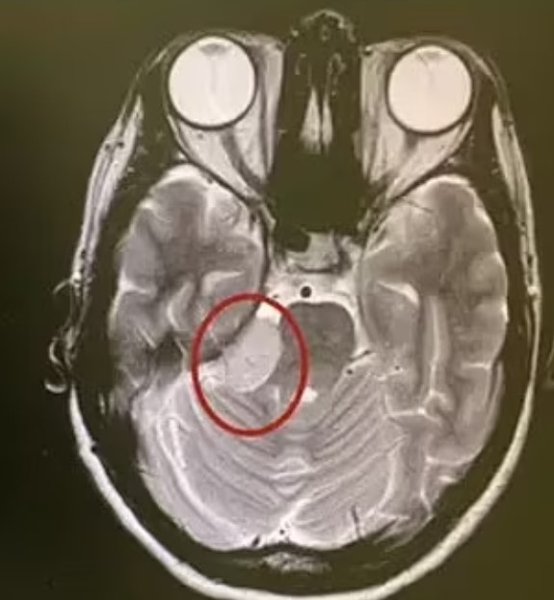

Во время следующего приема врачи диагностировали у женщины существование доброкачественной опухоли в головном мозге, которая давила на лицевой нерв. По словам медиков, размеры опухоли указывали на то, что она развивалась в течение 10 лет. Для того, чтобы избавиться от опухоли женщине предложили сделать операцию.

опухоль мозга

Врачи диагностировали у женщины существование доброкачественной опухоли в головном мозге, которая давила на лицевой нерв

Хотя Ванакер согласилась сделать операцию, она хотела выяснить, почему эту опухоль не обнаружили 10 лет назад. Врачи заявили, что судя по прошлым снимкам МРТ, эта опухоль была настолько крошечной, что ее скорее всего просто пропустили при осмотре.